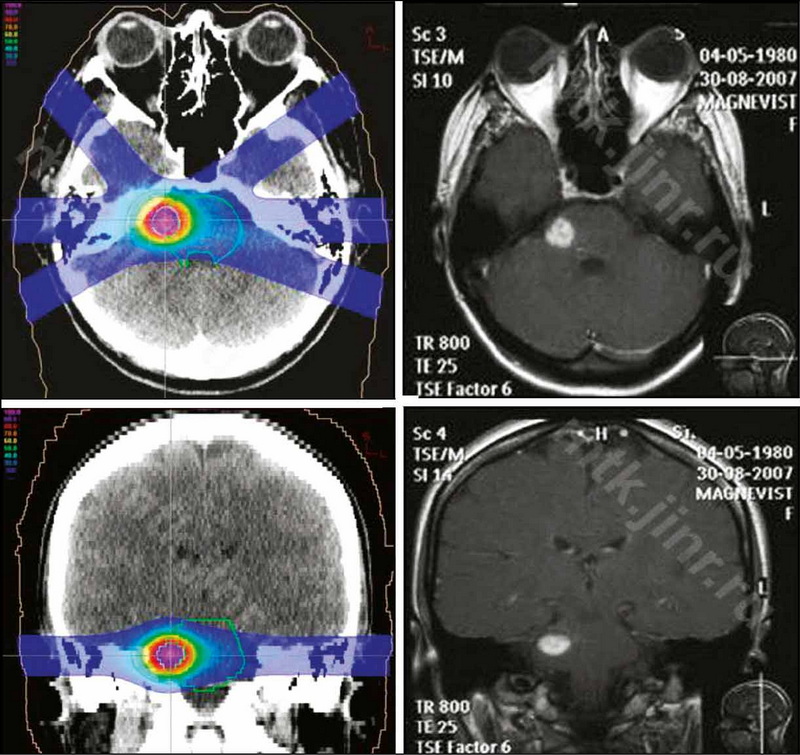

Cavernous malformations of the brain and modern views on their treatment

Cavernous malformations of the brain have become an increasingly common pathology in recent years, thanks to the advancement of modern methods of neuroimaging. Despite the benign nature of the course in most cases, these formations can cause convulsions and serious neurological disorders. Typically, clinical manifestations are caused by hemorrhages in the structure of the cavernous and surrounding parenchyma of the brain. The management strategy chosen for patients with cerebral cavernous malformations is determined by the type of malformation, its size, localization, the presence of repeated hemorrhages, and the clinical picture.

This literature review focuses on modern methods of treating cerebral cavernous malformations. The main methods of treatment for cavernous malformations of the brain, particularly surgical treatment, have been analyzed. If surgical intervention is not possible, alternative methods of treatment include radiation therapy, such as stereotaxic radiosurgery, and proton therapy, in cases of deep location of foci in functionally significant areas of the brain, which are characterized by the highest risk of complications. Thе possibilities, efficacy, and safety of stereotactic radiosurgical treatment are discussed, as well as the use of proton therapy in the treatment of cavernous malformations. Furthermore, radiation therapy has been shown to be beneficial for cavernous malformations.